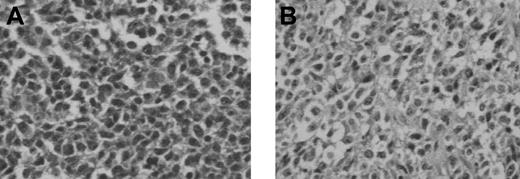

To select variants with better in vivo growth potential, 3 tumor cell lines were initially tested for in vivo growth after transfer into NOD/SCID mice. The 3 tumor cell lines tested included LCL-13271, MML-12933, and CML-14736. Results of these experiments are summarized in Table 3. Of these lines, only LCL-13271 demonstrated growth in vivo after intraperitoneal injection into mice (Figure 4). This particular cell line was isolated from a SLAad animal, 13271, that developed recipient-derived PTLD after a hematopoietic cell transplantation.35 Similar to the phenotype of some human lymphoma cell lines,38 LCL-13271 had a stable phenotype after 72 passages based on continued expression of CD2 and CD25 while lacking other T-cell markers such as CD3 and CD5 and lacking myeloid markers such as CD16 and CD172.

Histologic findings after in vivo transfer of LCL-13271 tumor cells in NOD/SCID mice. LCL-13271 injected intraperitoneally into NOD/SCID mice with tumor growth at 2 months in primary and secondary recipients. Abdominal tumor mass from NOD/SCID primary (A) and secondary (B) recipients of LCL-13271. Histologic findings were similar in morphology compared with the primary tumor (Huang et al35 ). Slides were viewed with an Olympus BX40 microscope (Olympus America) of sections stained with H&E medium (Hematoxylin Gill's Formulation no. 2, Fisher Diagnostics; Eosin-Y, Richard-Allan Scientific) using a lens at 400×. Images were acquired using a Hitachi charge-coupled device color camera (Hitachi Kokusai Electric America, Woodbury, NY) model HV-C20 3-CCD, and were processed with ACDSee version 4.0 software (ACD Systems International, Victoria, BC).

LCL-13271 cells were initially injected intraperitoneally into 4 NOD/SCID mice at a dose of 1.5 × 107 cells. After 2 months, animals had palpable masses that were harvested and evaluated by culture and histology. Abnormal cells with pleiomorphism and heterochromatic nuclei were found and were similar to what was seen in the primary tumor (Figure 4). Cell suspensions from these tissues were confirmed as LCL-13271 in origin based on expression of CD2 and on the lack of other T-cell and myeloid markers. For secondary transfer, these cells were then injected into 3 additional NOD/SCID mice at a dose of 5 × 107 cells, and these animals also grew palpable tumors. Tissues were harvested, processed, cultured, and frozen.